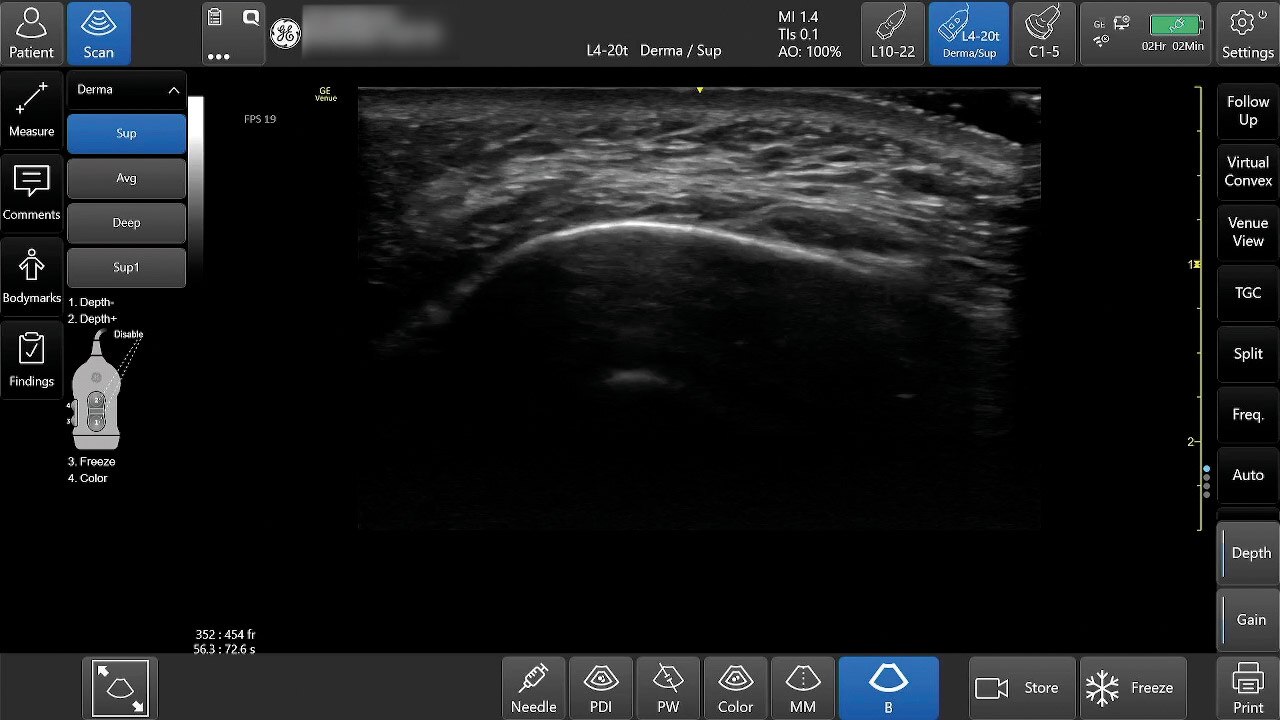

Flow Profiles

Reduce exam time by 56% with Flow Profiles. Dramatically simplifies color and pulsed-wave Doppler optimization by utilizing predefined and optimized settings.